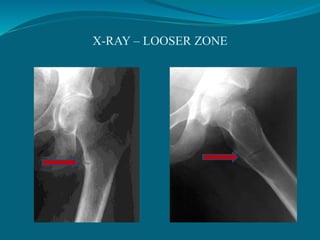

 Osteoid seams generally in relation to 1

trabeculae but in one or more bones due to

very poor mineralization contain very large

ribbion like radiolucent area of osteoid seams

k/a looser’s zone/ umbauzons/ milkman

pseudofracture (VIRTUALLY DIAGNOSTIC

of osteomalacic syndrome)

X-RAY – LOOSER ZONE